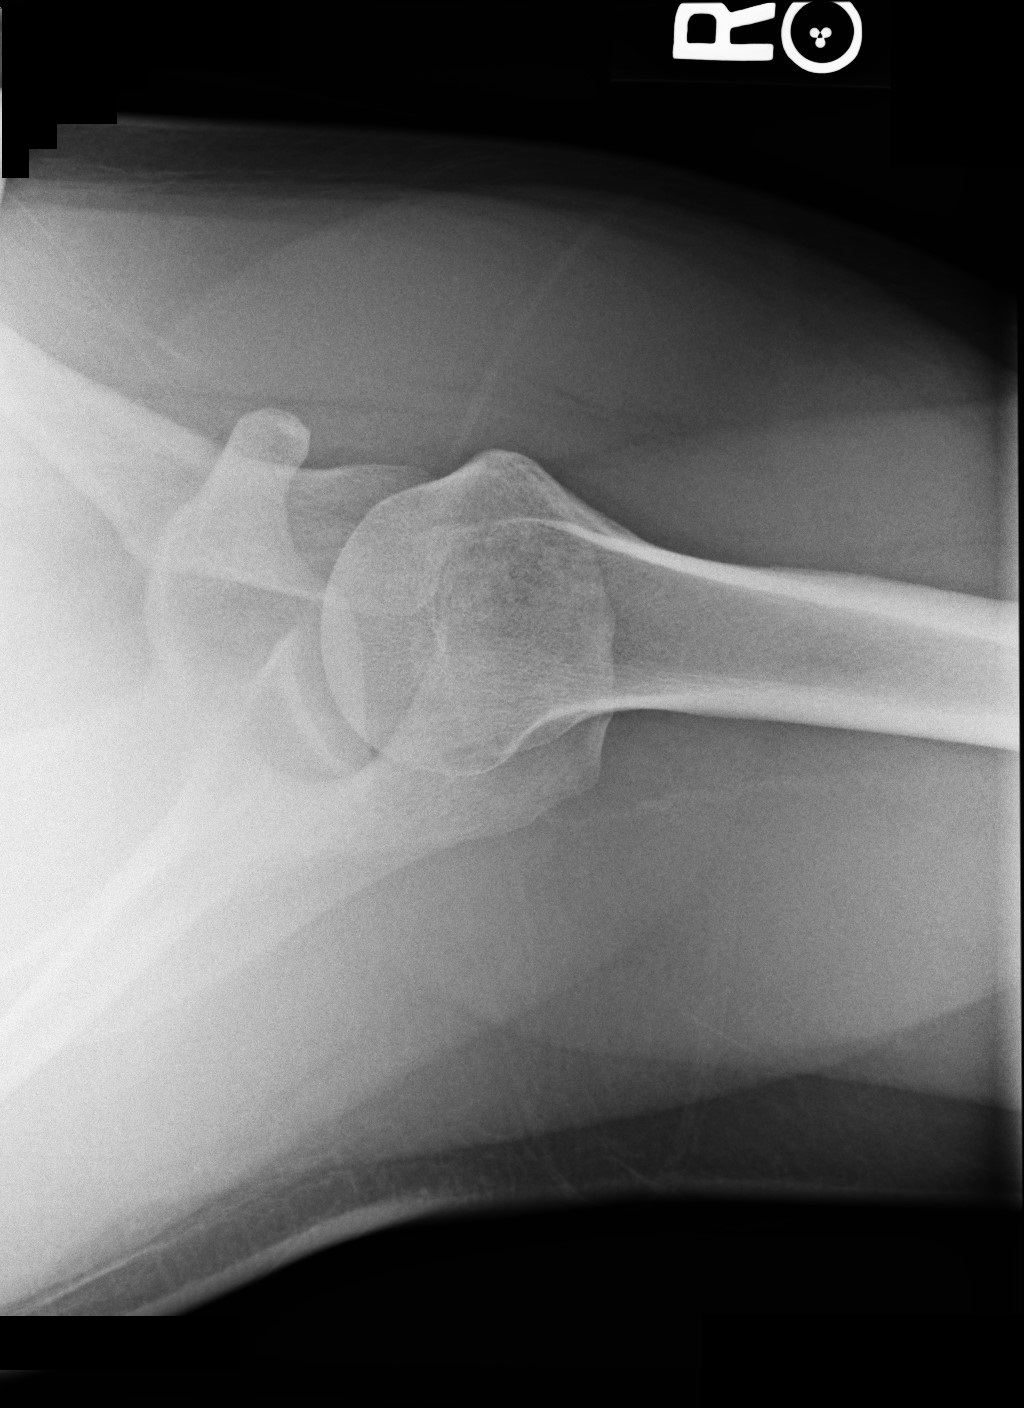

Radiographs of the right shoulder were taken (Figures 1-3).

Figure 3. Scapular Y view of right shoulder.Based on the history, physical examination findings, and radiographs, which one of the following is the most likely diagnosis?